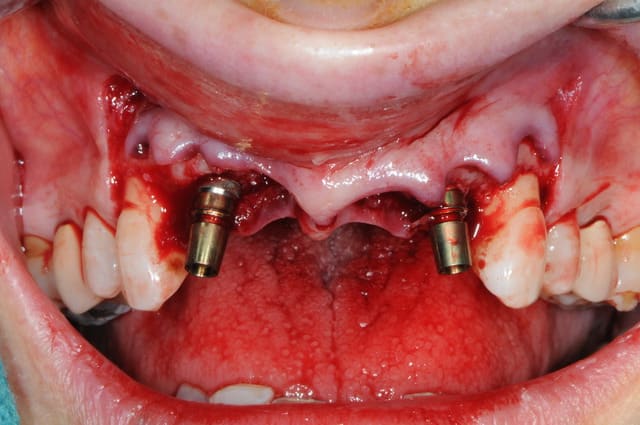

la chir...

extraction de 12 et 22 pour commencer et pour connaitre la limite maxi d'implantation dans la crête osseuse.

grosse déception quant à la table externe au niveau de 11

pour les axes, j'avoue que je me suis fait avoir comme une bleusaille (mais bon, j'en suis une), je me suis un peu laisser embarquer par l'axe des alvéoles. c'est dure l'implanto.